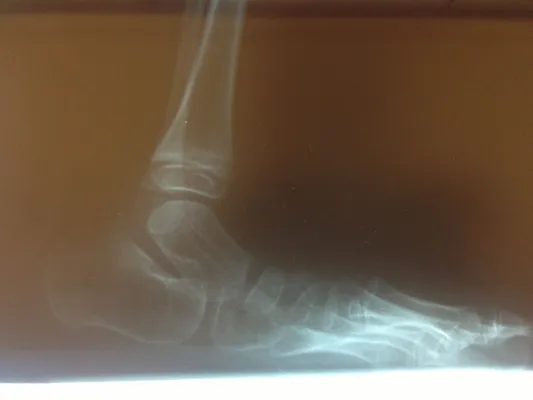

Below are x-rays of a foot pre-operatively (left) where the black line indicates and plantarflexed (downward directed) talus bone and post-surgical repair with a subtalar joint implant and lenthening of the calf muscle which allows the calcaneus (heel bone) to set underneath the talus and the implant keeps the talus from subluxing off the calcaneus and now the talus is more inline with the front of the foot (right).